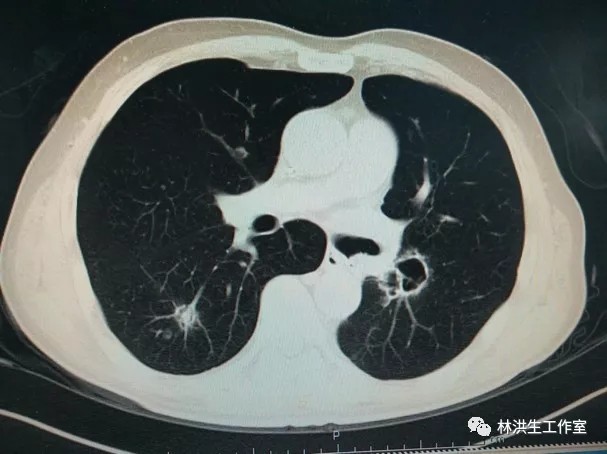

【诊断】左肺下叶腺癌术后双肺转移

【现病史】患者2014年7月就诊于中国医学科学院肿瘤医院诊断左肺下叶腺癌行手术切除pT3N2,术后辅助化疗后不到1年2015年5月复查发现双肺转移,基因检测阴性,中西医结合至今,病灶进展缓慢,体力状况PS 100分。

2017-10-21中药治疗后:双肺多发转移瘤大者增大至约2.6*2.3cm